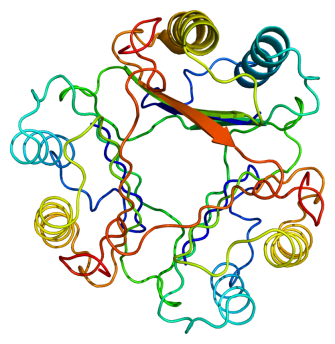

The brains of those who were in the early stages of Alzheimer’s had the crucial enzyme MIF (macrophage migration inhibitory factor) that was damaged. The enzyme, which is related to inflammation response and insulin regulation, was injured through a process called glycation. The researchers believe that the tipping point for Alzheimer’s to progress may be when MIF is damaged through glycation. As Alzheimer’s advances, so does the glycation of the MIF enzymes.

“Normally MIF would be part of the immune response to the build-up of abnormal proteins in the brain, and we think that because sugar damage reduces some MIF functions and completely inhibits others that this could be a tipping point that allows Alzheimer’s to develop.”-Professor Jean van den Elsen (University of Bath), commenting about the study in its press release.